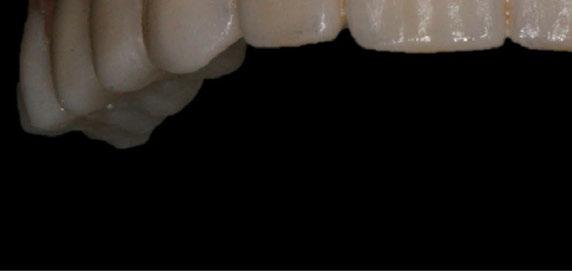

5. Fase protésica definitiva

A los 4 meses, se retiró la prótesis provisional, verificando la